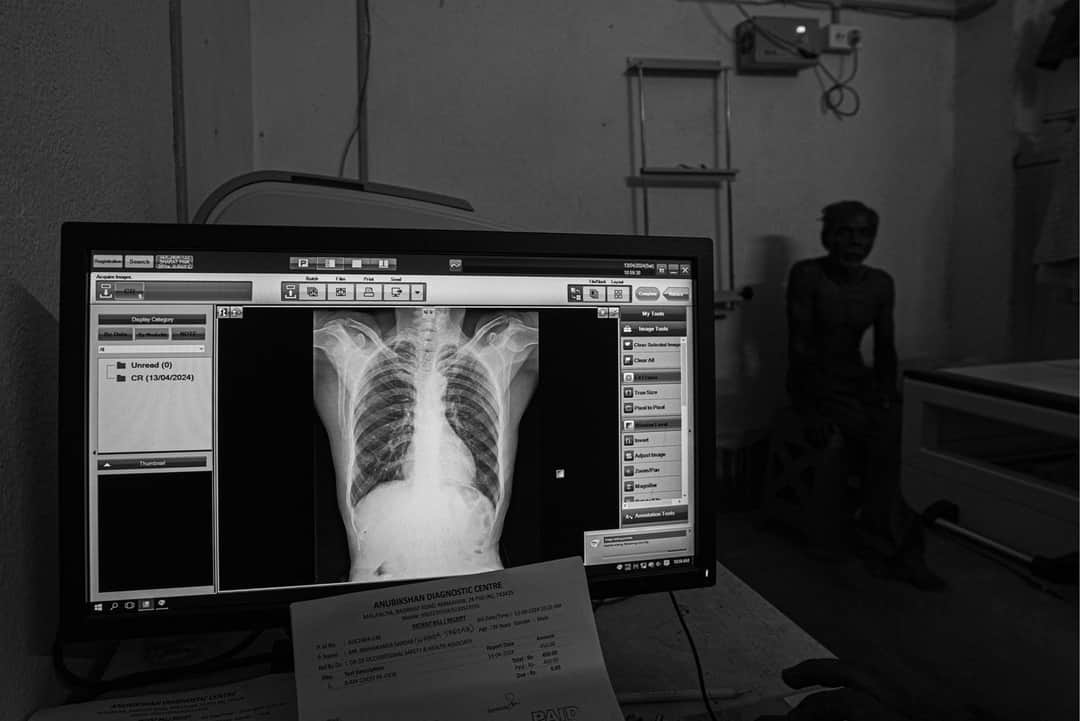

نومبر ۲۰۲۲ میں ۵۵ سال کے مانک میں سلیکوسس کی علامت پائی گئی، جو کہ ایک لاعلاج مرض ہے۔ ’انتخابات میں میری کوئی دلچسپی نہیں ہے،‘‘ وہ کہتے ہیں۔ ’’مجھے بس اپنی فیملی کی فکر ہے۔‘‘

نب کمار منڈل بھی سلیکوسس کے مریض ہیں۔ وہ کہتے ہیں، ’’انتخابات جھوٹ کی بنیاد پر لڑے جاتے ہیں۔ ہمارے لیے ووٹ ڈالنا روزمرہ کے دوسرے کاموں جیسا ہی ہے۔ کوئی جیتے یا ہارے، ہمیں اس سے کوئی فرق نہیں پڑتا۔ ہمارے حالات نہیں بدلیں گے۔‘‘

یہ دونوں ہی اپنی گرتی ہوئی صحت اور ان فیکٹریوں میں سلیکا کے ذرات کے درمیان سانس لینے کی وجہ سے آمدنی میں ہوئے نقصان کو برداشت کر رہے ہیں، جن میں انہوں نے ایک ڈیڑھ سال کے لیے بیچ بیچ میں کام کیا تھا۔ انہیں کسی قسم کا معاوضہ اس لیے نہیں مل پایا، کیوں کہ زیادہ تر ریمنگ ماس فیکٹریاں، کارخانوں کے ڈائریکٹوریٹ کے ساتھ رجسٹرڈ نہیں ہیں، اور اگر دو چار ہیں بھی تو وہ اپنے مزدوروں کے نام کوئی تقرری نامہ یا شناختی کارڈ جاری نہیں کرتی ہیں۔ سچ تو یہ ہے کہ زیادہ تر فیکٹریاں یا تو غیر قانونی ہیں یا جزوی طور پر ہی قانونی ہیں، اور ان میں کام کرنے والے مزدوروں کو رجسٹرڈ نہیں کیا گیا ہے۔